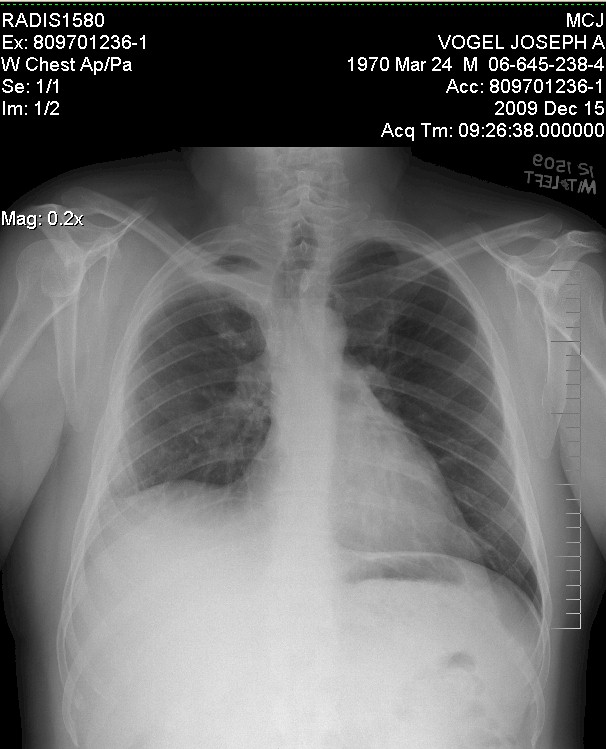

Example of a real "Normal Lung" of a 40-year old male:

X-Ray of my chest done by Solantic and indicated as

"normal lung" in October 2008:

When you compare this to the example of a real normal one above, you can see how

the right side it shifted up and the upper right area is not as dark.

The dark area indicates "air" in the lung (when you get a chest x-ray they ask

you to breath in deep). Also note on the left hand side you see more of a

full lung, remembering that the heart is in front of the lung on that side so it

does not show up as dark.

But you can tell something is not quite right with the right lung presentation.

Nonetheless, the Solantic doctor indicated it as "normal

lung".

X-Ray of my chest done by Mayo and indicated as

"abnormal lung" in October 2009:

So, as you can see, basically the EXACT same!

Which in one way was good since it had not gotten worse, BUT it was the exact

same so Solantic totally missed it!

Arg!